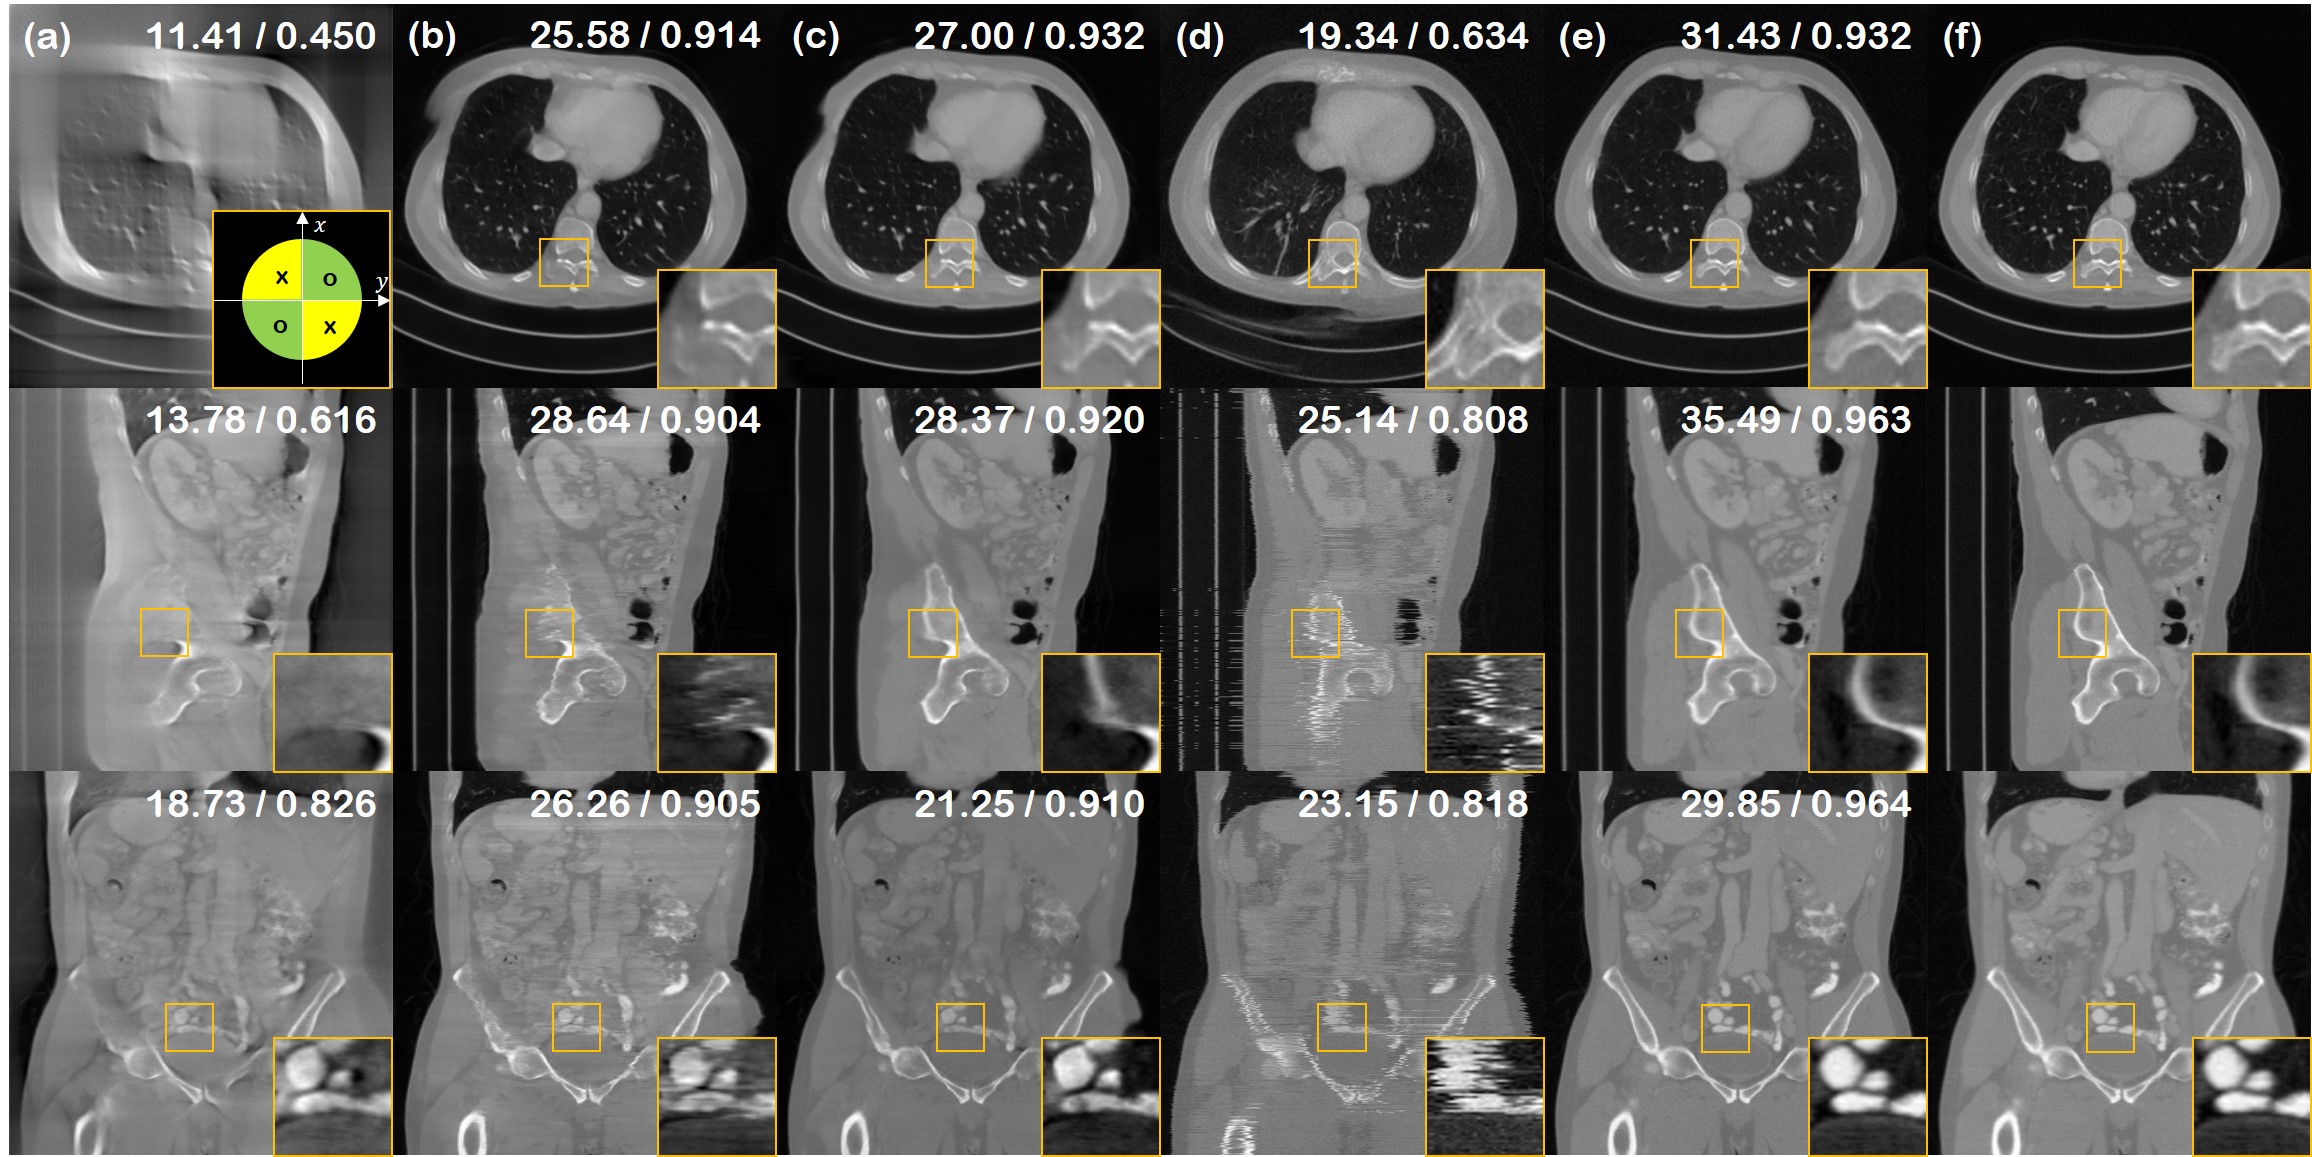

Refer to caption

Figure 6: 4-view SV-CT reconstruction results of the test data (First row: axial slice, second row: sagittal slice, third row: coronal slice). (a) FBP, (b) ADMM-TV, (c) Lahiri et al. [16], (d) Chung et al. [5], (e) proposed method, (f) ground truth. Green lines in the inset of first row (a): measured angles.

Figure 7: 2-view SV-CT reconstruction results of the test data (First row: axial slice, second row: sagittal slice, third row: coronal slice). (a) FBP, (b) proposed method, (f) ground truth. Green lines in the inset of first row (a): measured angles.

4-view sparse view tomographic reconstruction is presented in Fig. 6. Furthermore, we demonstrate that we can even perform 2-view reconstruction, as can be seen in Fig. 7. In this regime, the information contained in the measurement is very few and sparse — clearly not sufficient for achieving an accurate reconstruction. As we are leveraging the generative prior however, we can sample multiple reconstructions that are 1) perfectly measurement feasible, and 2) looks realistic. Although this might not be of significant importance in the medical imaging field, it could greatly impact fields where approximate reconstructions from very limited acquisitions are necessary.